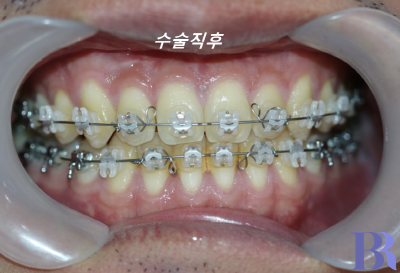

1년정도의 술전교정을 마친 후

수술직후 모습입니다.

아래턱이 많이 들어갔고

얼굴이 잛아졌습니다

수술 직후 치아 모습입니다

반대교합이 잘 해소가 되었네요

교합도 안정적으로 맞물립니다.

교합도 아주 긴밀하게

수술이 잘되었습니다